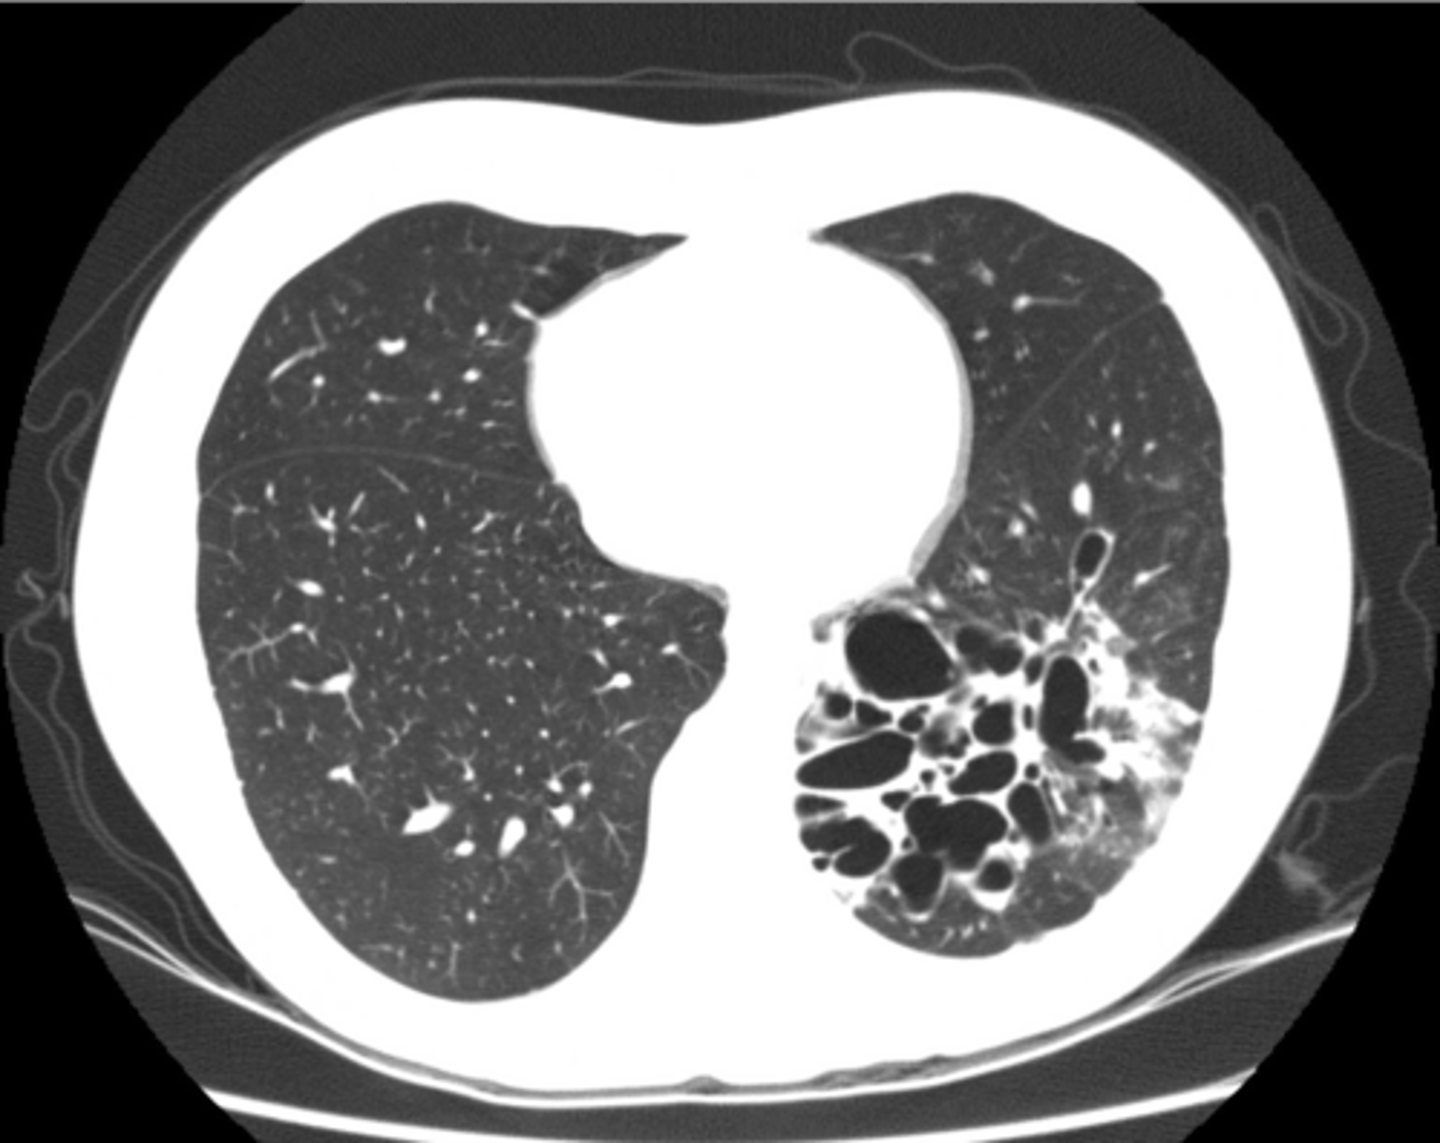

Bronchiectasis

knowt flashcard image

Condition that can cause bronchiectasis

Cystic fibrosis